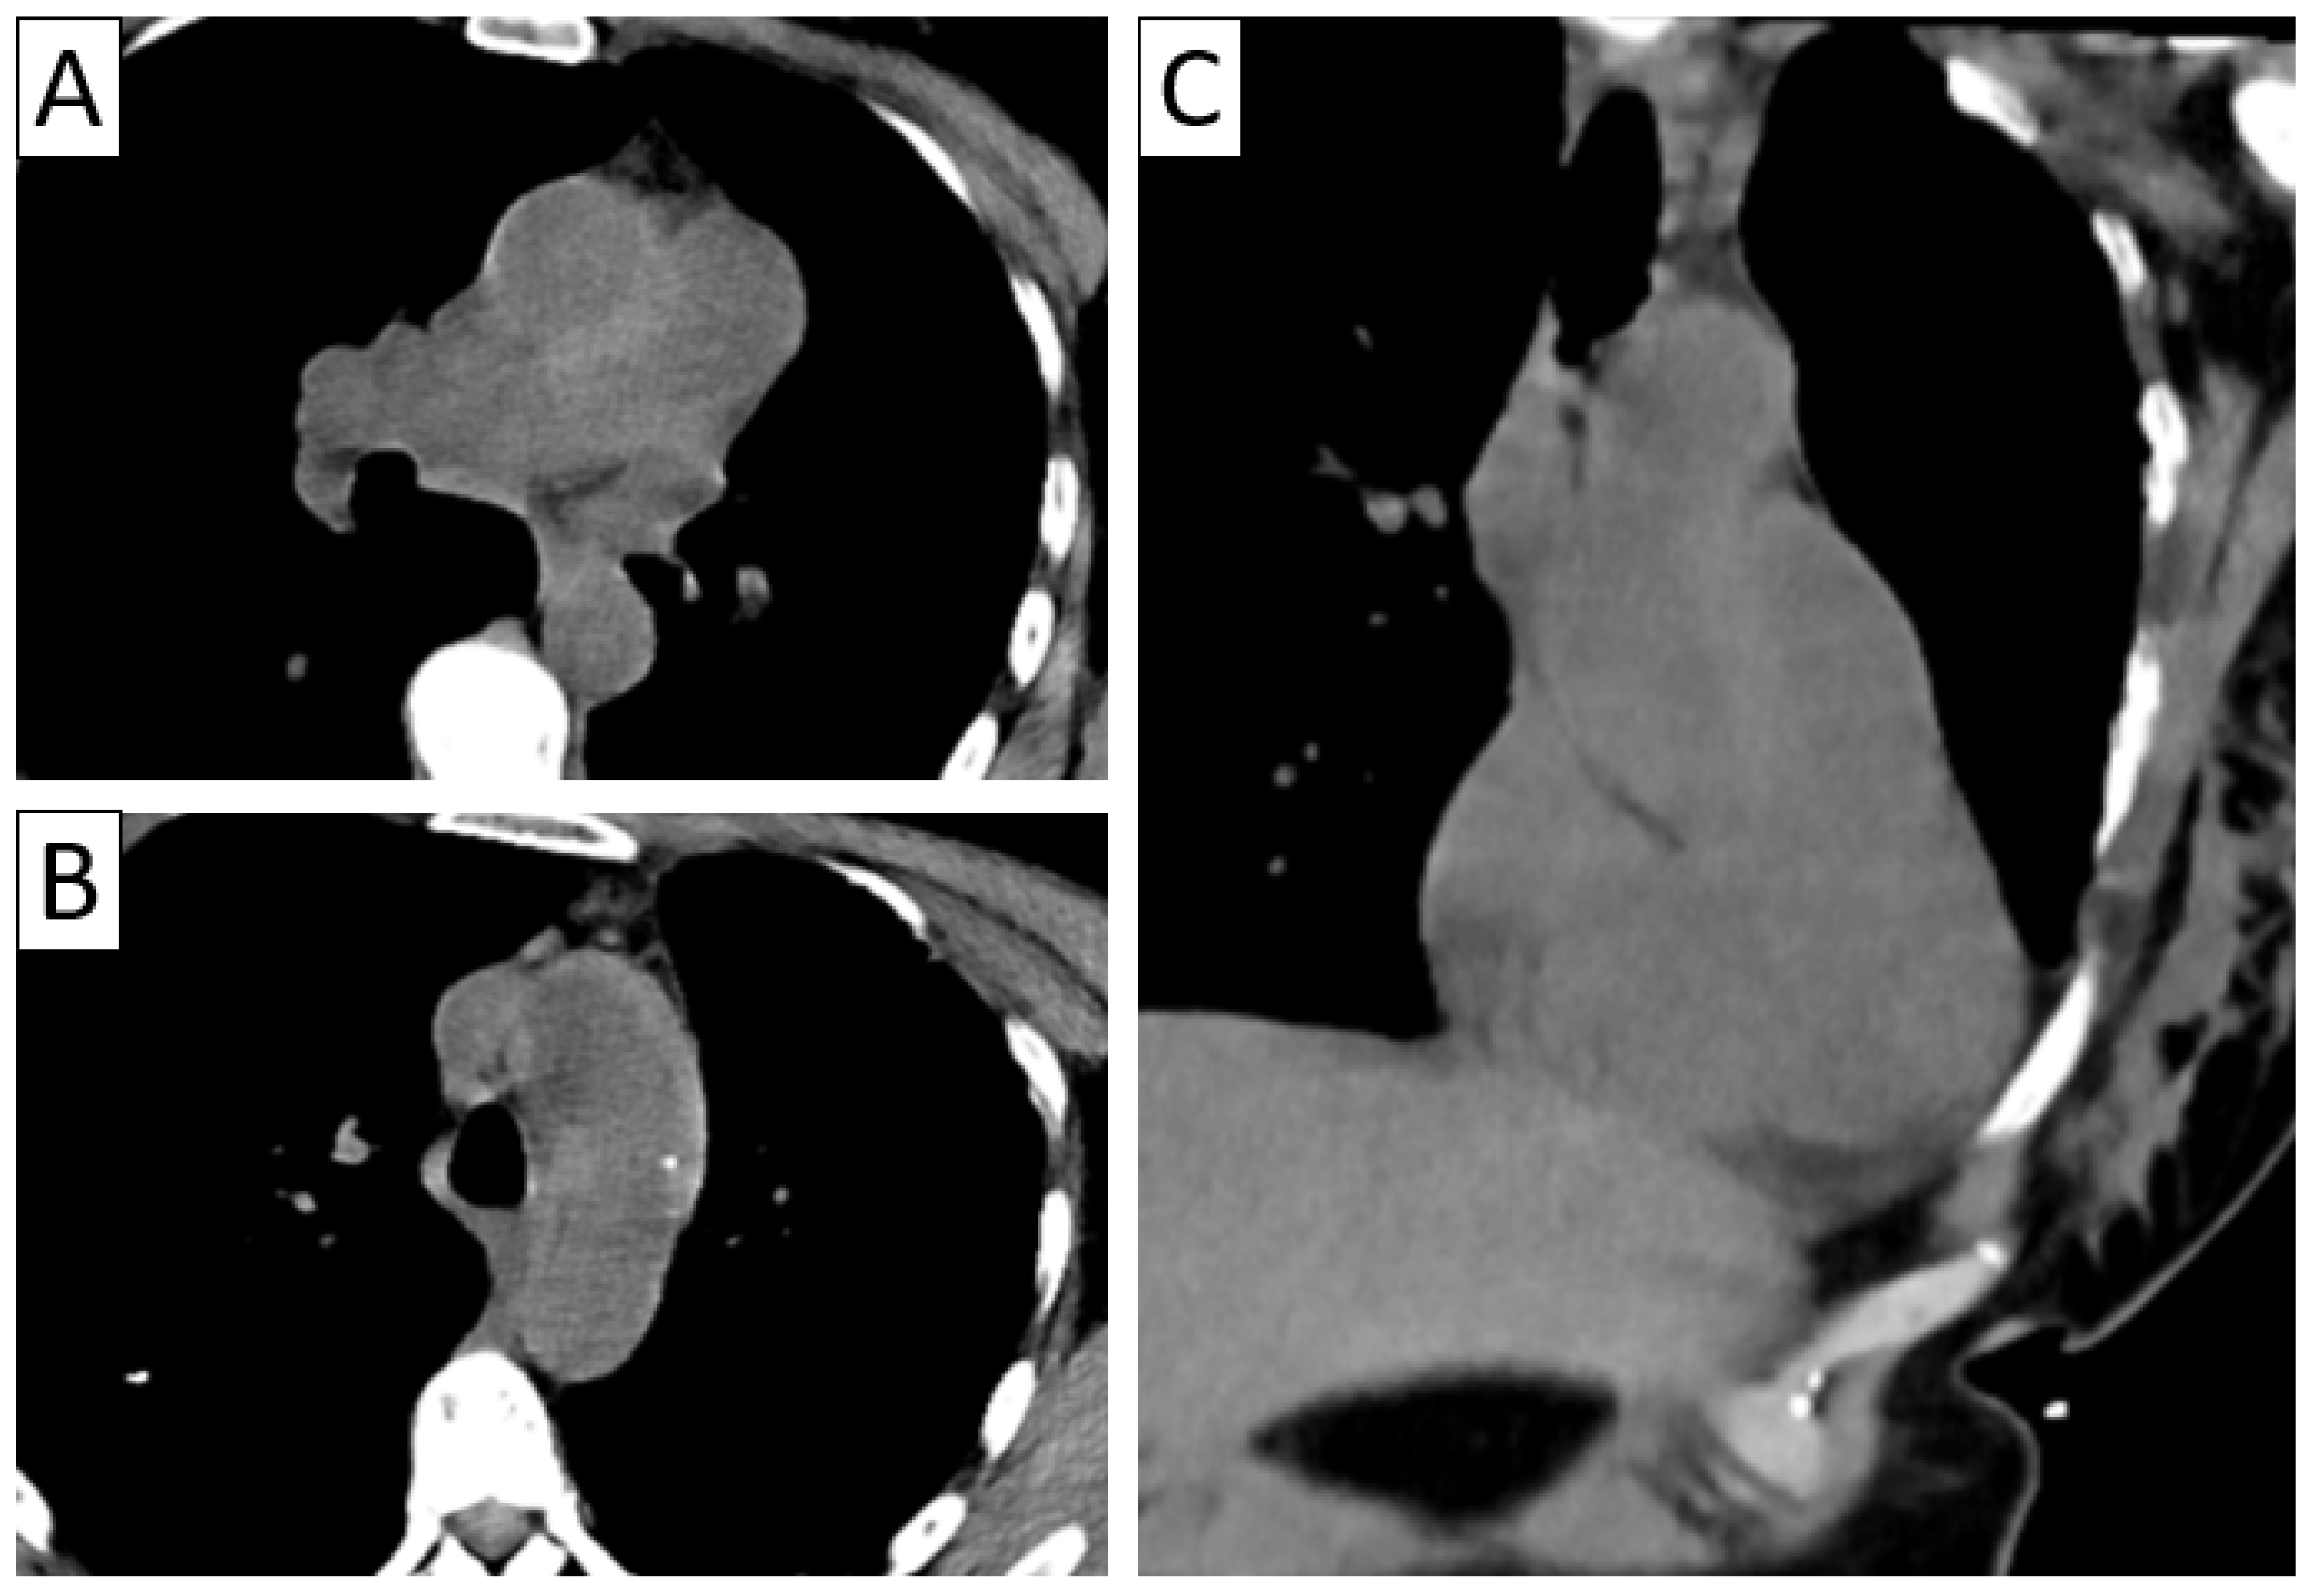

| CTA | Circumferential parietal thickening Vessel wall enhancement | Circumferential parietal thickening Vessel wall enhancement Luminal stenosis or narrowing |